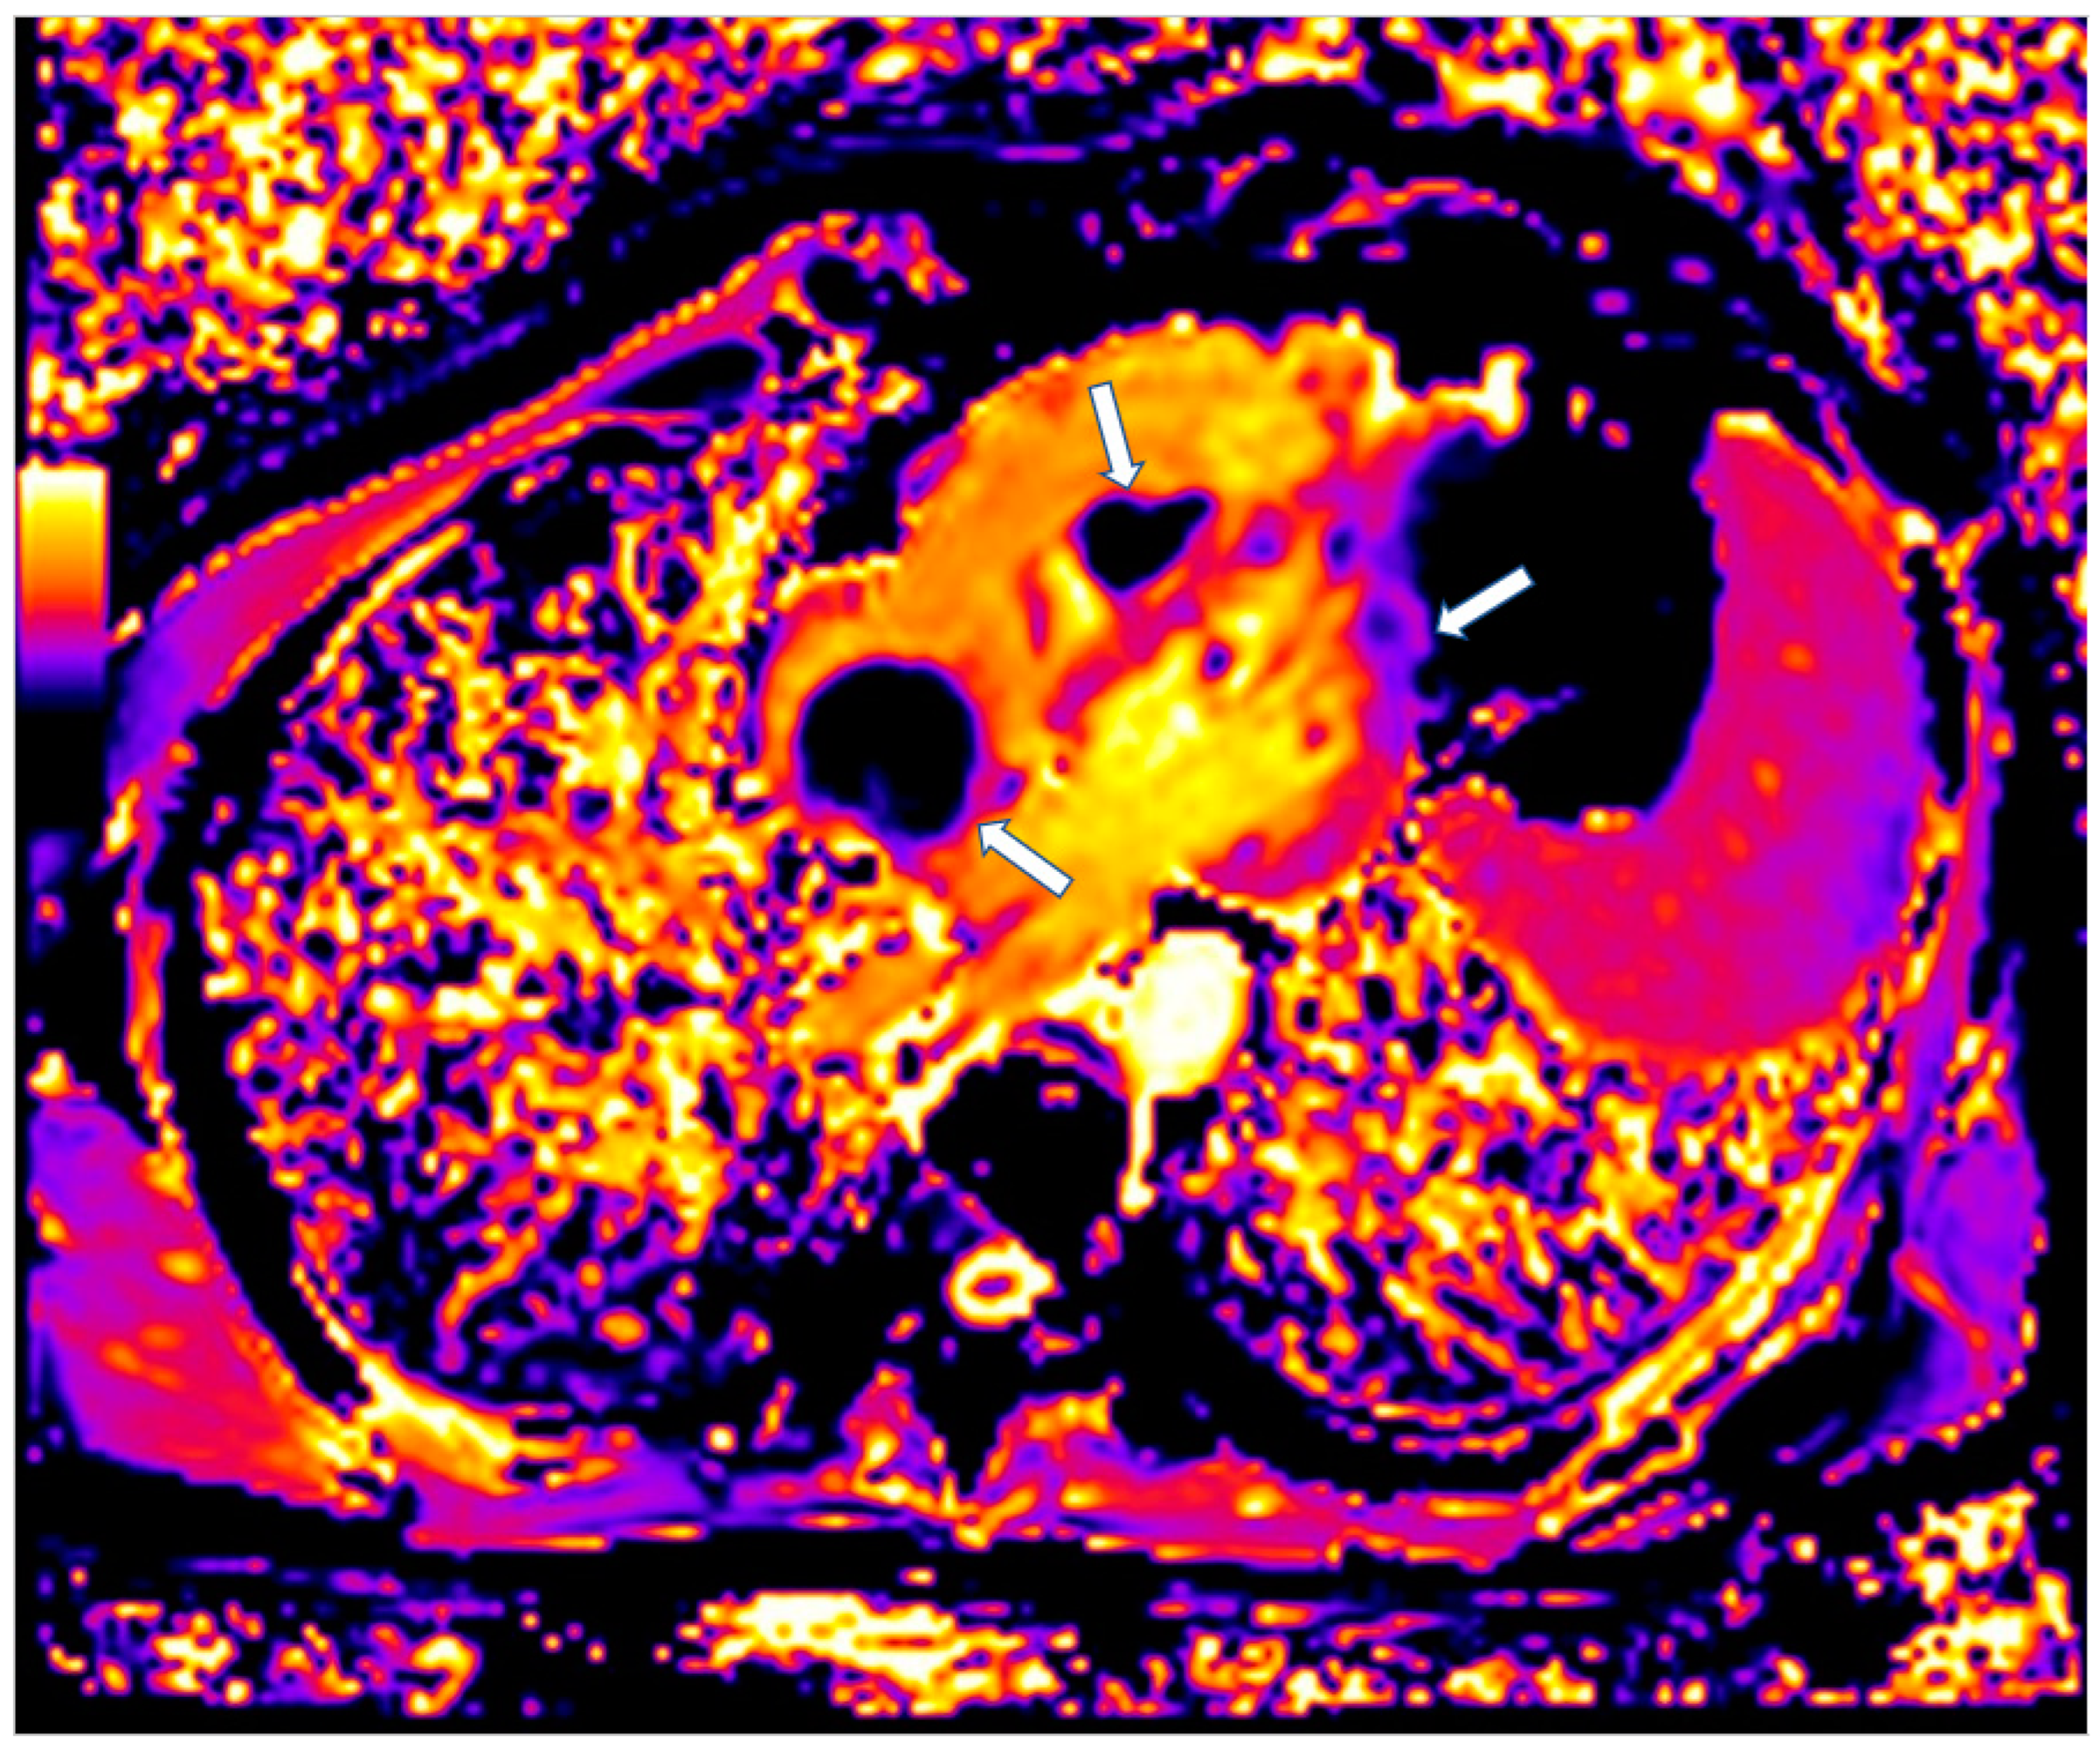

CMR is also of value in the detection of intracardiac thrombi. Usually, the majority of thrombi is small, homogeneous, often associated with venous catheters and typically hypointense on first-pass perfusion, due to lack of vasculature [96]. Compared to thrombi, malignant tumors tend to be larger with first-pass perfusion abnormalities and LGE [96,97]. Parametric mapping has also demonstrated important diagnostic value (Figure 7) [97].

Figure 7.

Four chamber T1 mapping showing LV infiltration and RV-Right atrium masses (arrows) due to melanoma.